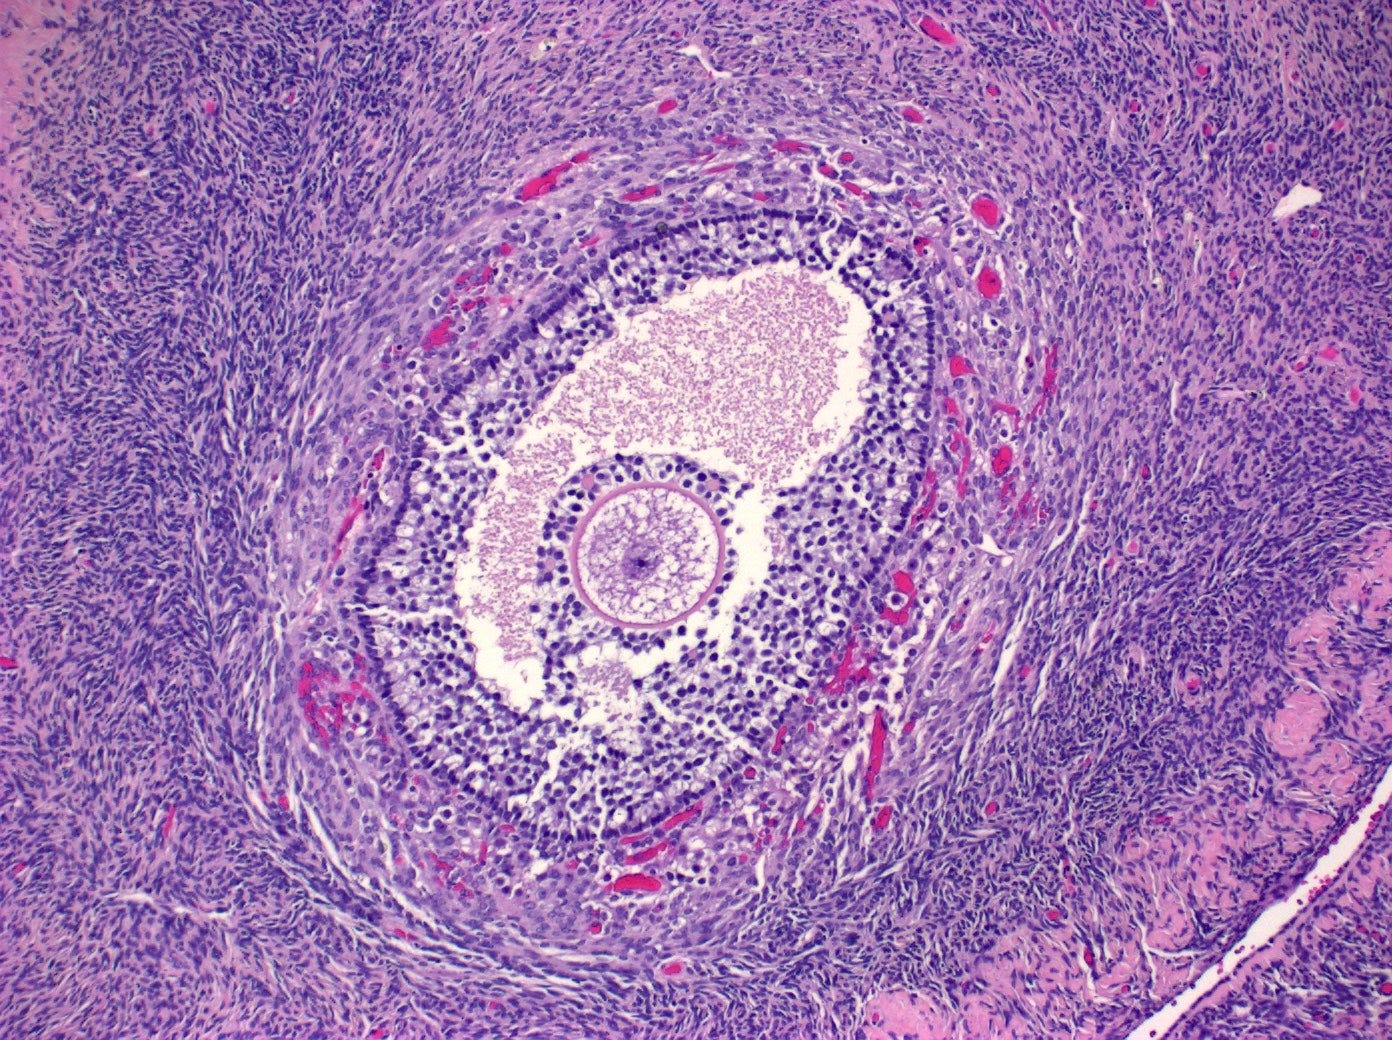

Ovaries are essential to the fertility and cycling of reproductive activity in women and girls by controlling the development of the dominant follicle (which contains the developing ovum or egg) and producing estrogen and progesterone hormones.

Most ovarian cancers are epithelial, but most testicular tumors derive from germ cells or sex cord stroma. Many ovarian cancers arise, in fact, from the fallopian tubes or the uterus, not from the ovaries themselves, as will be discussed in a future essay.